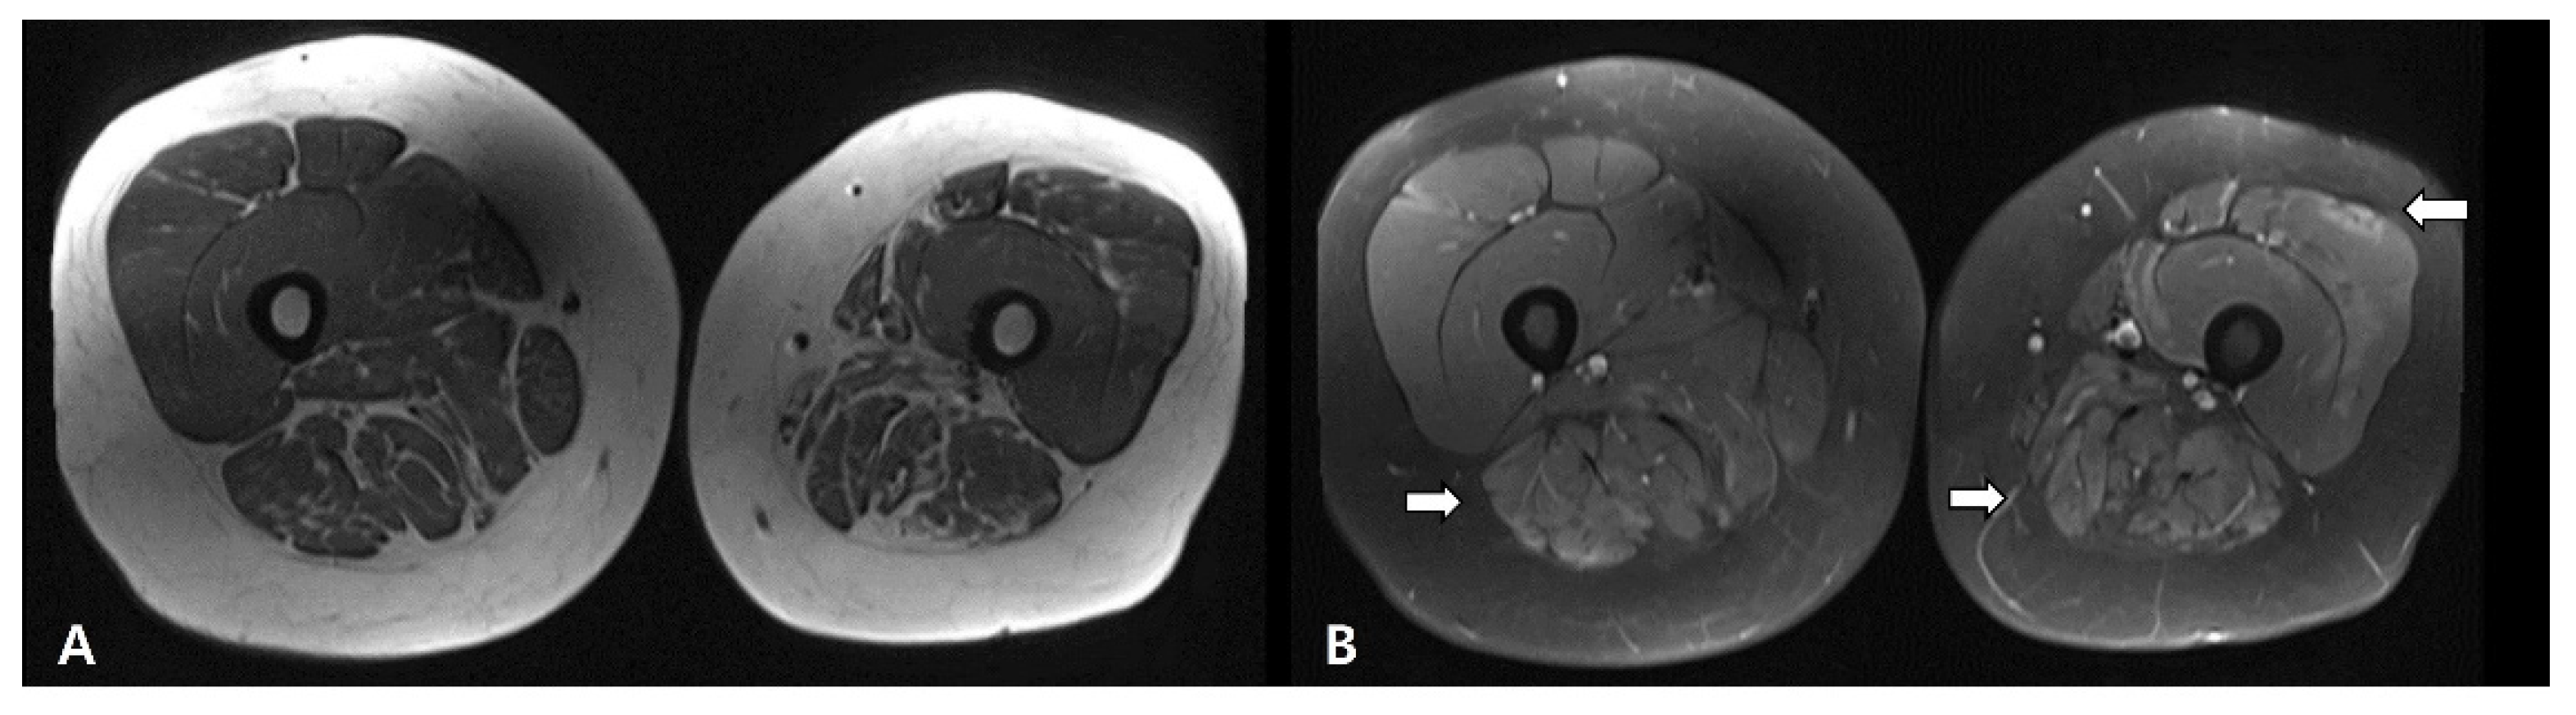

2. Case Presentation